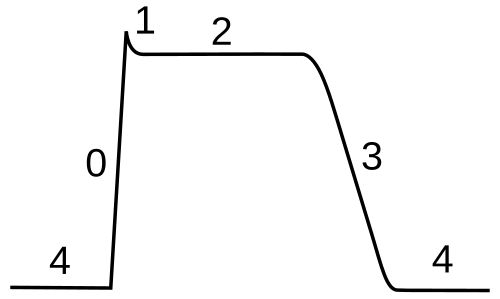

Action potential

In physiology, an action potential is the brief (about one-thousandth of a second) reversal of electric polarization of the membrane of a excited cells such as nerve cell (neuron), muscle cell, endocrine cell and so on.[30]. In neurons, an action potential happens when a neuron sends information down an axon, away from the cell body. In other types of cells, they activate intracellular processes. In muscle cells, for example, an action potential produces the contraction required for all movement. In beta cells of the pancreas, they induce release of insulin.[31] Action potentials in neurons are also known as "nerve impulses" or "spikes", and the temporal sequence of action potentials generated by a neuron is called its "spike train". A neuron that emits an action potential is often said to "fire"[32].

Action potentials are generated by specific voltage-gated ion channels embedded in a cell's plasma membrane.[33] These channels are shut when the membrane potential is near the resting potential of the cell, but stimulation of the cell by neurotransmitters or by sensory receptor cells partially opens channel-shaped protein molecules in the membrane. Sodium diffuses into the cell, shifting that part of the membrane toward a less-negative polarization. If this local potential reaches a critical state called the threshold potential (measuring about −60 mV), sodium channels open completely. Sodium floods inside the cell quickly depolarizes to an action potential of about +55 mV. The declining phase of the action potential is from the closing of sodium channels and the opening of potassium channels, which let a charge about equal to the stage which the cell leaves in the form of potassium ions. Therefore, protein transport molecules pump sodium ions out of the cell and potassium ions in. This restores the original ion concentrations and the membrane is ready for a new action potential.